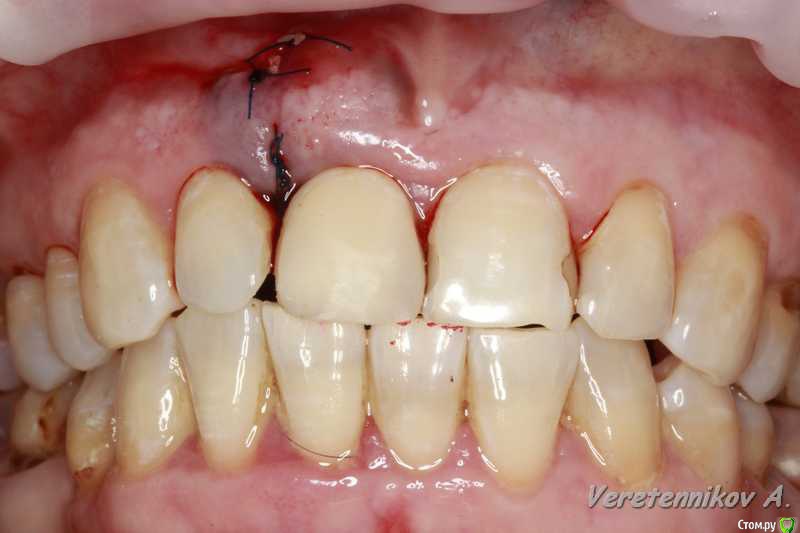

Популярный пост an_ver Опубликовано 15 января, 2016 Популярный пост Поделиться Опубликовано 15 января, 2016 11,жил долго и счастливо..но тут Новый год(((, скол ниже уровня ЦЭС на 3 мм...от экструзии отказалась.Из своего зуба сколхозил шаблон,чтоб наверняка. Удалил,кюретаж,вестибулярка целая, SPI 4.2*13 мм,с бугра ССТ,на всякий)),в щели Апатос,врем.абатмент,врем.коронка из своего зуба. 1ч.20мин.)) 27 Ссылка на комментарий

k.t.m. Опубликовано 15 января, 2016 Поделиться Опубликовано 15 января, 2016 в щели апатос,сст в сформированный карман! Андрей красиво и все по пунктам,как так вышло что сосочек порвался?может не стоило так глубоко сст заводить? 1 Ссылка на комментарий

an_ver Опубликовано 16 января, 2016 Автор Поделиться Опубликовано 16 января, 2016 (изменено) в щели апатос,сст в сформированный карман! Андрей красиво и все по пунктам,как так вышло что сосочек порвался?может не стоило так глубоко сст заводить?Чесно,фиг знает((( тока счас обратил внимание,наверно 15С орудовал глубоко (набор Деплер для туннеля в клаве был),((( немного лоскут перфорнул...если кто заметил,решил глубже завести ластик сст Изменено 16 января, 2016 пользователем an_ver Ссылка на комментарий